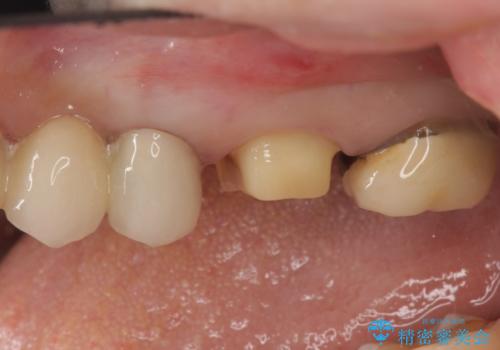

- 左上の奥歯がたまにしみるとのことで来院。視診・レントゲン画像より明らかに劣化した不適な修復物を確認しました。

同じ材料で同じように修復し直してもまた同じような予後になることが予想されるため、適合の良いセラミックインレーでの治療を提案させていただきました。

しかし向かい合わせになる歯の咬みこみが強く、インレーでは破折してしまうリスクが高いと予想し、より強固なクラウンで修復することになりました。